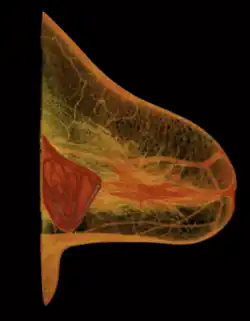

Skandál, který silně ovlivnil legislativní požadavky v Evropě

Mediálně je známý skandál s prsními implantáty od francouzského výrobce Poly Implant Prothèse (PIP). Tento výrobce v cílené, skryté a podvodné snaze snížit náklady na výrobu, vyráběl prsní implantáty z levnějšího průmyslového silikonu (který nebyl schválen pro lékařské použití). Nekvalitní a zdravotně závadný silikon nakonec vedl ke zvýšení počtu různorodých zdravotních komplikací. V roce 2011 bylo jen ve Francii cca 30000 pacientkám v této souvislosti doporučeno preventivní odstranění implantátů vyrobených firmou PIP. V důsledku tohoto skandálu Evropská komise úplně přepracovala předpisy pro zdravotnické prostředky s cílem zajistit vysokou úroveň bezpečnosti a obnovit důvěru veřejnosti ve zdravotnictví.[4][5][6][7]

Ruptura prsního implantátu

Ruptura prsního implantátu -